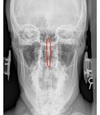

APOM ANATOMICAL LANDMARKS

maxillary sinus

29

frontal sinus

30

nasal aperature

31

nasal spine + septum

32

lower teeth

33

upper teeth

34

mandible

35

jugular process

36

A-P open mouth

rim of foramen magnum

37

anterior arch c1

38

posterior arch c1

39

A to P open mouth

lateral mass of c1

40

transverse process c1

41

medial inferior tip of occipital condyles

42

mastoid air cells

43

A-P open mouth view

pedicle shadow c2

44

spinous process c2

45

eop-iop

46

atlantal-axial joint space

47

vertebral bodies c2-c7

48

inferior articular surface c1

49

superior articular surface c1

50

A-P cervical

uncinate process of cervical vertebra

51

occipital-atlantal joint space

52

odontoid process